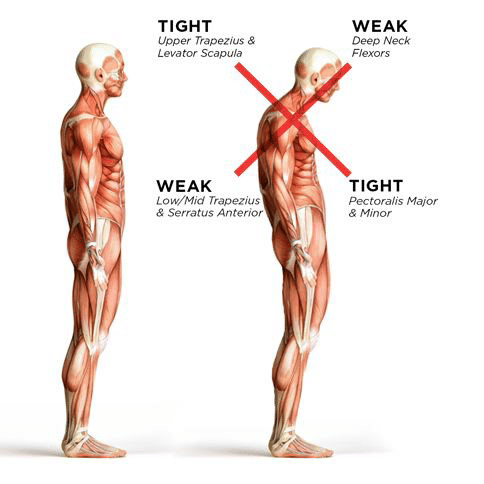

Our chest muscles and the muscles in the back of our head and neck tend to get tight when we have a forward head posture. Ask your therapist to help you learn to stretch these muscles!

Our chest muscles and the muscles in the back of our head and neck tend to get tight when we have a forward head posture. Ask your therapist to help you learn to stretch these muscles!